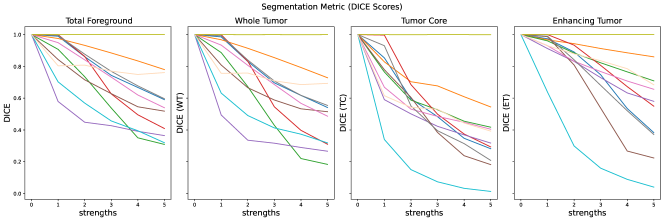

The results for all strengths are given in Figs. A.1-A.4. In Tab. 5 - 8, the results for distortions of maximal strength (s=5) are summarized.

The segmentation scores (see Tab. 5, and Fig. A.4) for all three classes are very similar. Intensity shift has no effect due to preprocessing with z-score normalization. The effect of elastic deforms and ghosting artifacts on the segmentation are very limited. Gaussian noise and stripe artifacts most strongly impair segmentation. Translated segmentations have decreasing overlap and thereby very low DICE scores.

Replace artifacts remain underestimated by most similarity metrics. For those artifacts, that resemble structures of diagnostic interest, the evaluation of segmentations with a specific segmentation model is useful. In our evaluation, we use a segmentation model, that was trained to detect different tumor regions. It successfully detects replace artifacts, where the tumor is doubled or removed.